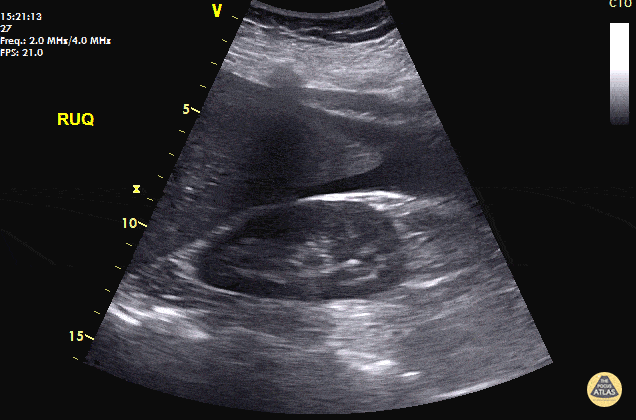

40 y/o F with abdominal pain, syncopal, +HCG. POCUS reveals free fluid in RUQ at inferior pole of the kidney and caudal tip of liver. Patient taken immediately to the OR and 800mL of blood evacuated. A left fallopian ectopic pregnancy was found. Always look for free fluid at the inferior pole of the kidney. POCUS saves lives. Dr. Cian McDermott - Dublin, Ireland